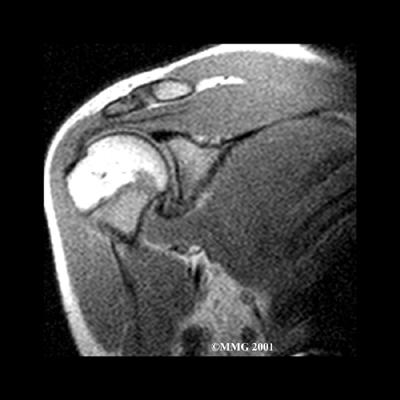

As your ability to move your shoulder increases, your doctor may suggest additional tests to differentiate between primary adhesive capsulitis and secondary adhesive capsulitis (from an underlying condition, such as impingement or a rotator cuff tear). Probably the most common test used is magnetic resonance imaging (MRI). An MRI scan is a special imaging test that uses magnetic waves to create pictures that show the tissues of the shoulder in slices. The MRI scan shows tendons and other soft tissues as well as the bones.